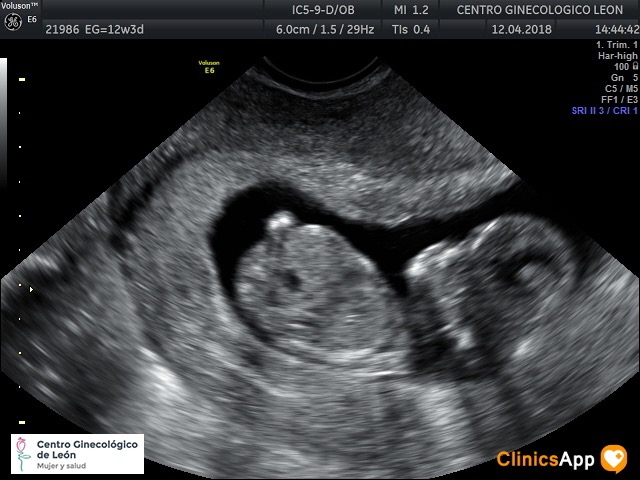

Ecografías del 12 de abril de 2018